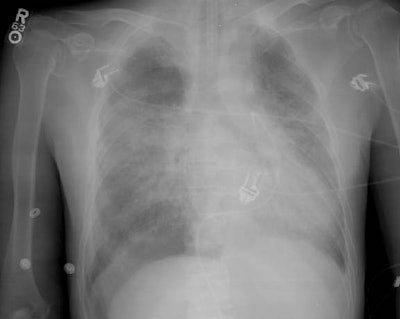

Right Pneumothorax with a Deep Sulcus Sign:

The images below are from a patient in the intensive care unit. The patient was admitted for radiation pneumonitis following radiation therapy for bronchogenic carcinoma. There is an endotracheal tube, and a Swan-Ganz catheter which was placed via a femoral venous approach.

On the initial film, the right costophrenic sulcus was cut off the film, but was suspicious for a "deep sulcus sign"- an indication of a pneumothorax in a supine patient. A repeat examination (below initial image) was performed which nicely demonstrated the "deep sulcus" on the right, as well as a pleural line in the right upper lung indicating that the pneumothorax had enlarged in the interval between the two films. This case demonstrates the need to include the costophrenic angles on all portable films.

Initial image: